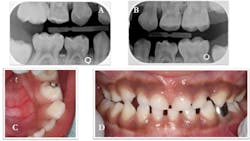

A three-year-old Hispanic male came to the clinic for his first dental visit. He was a well child without significant medical issues, and he regularly saw his pediatrician for well-child checks. The mother and patient denied any history of orofacial or dental symptoms, but mom was “concerned about a cavity in his bottom teeth.” The child was highly reactive to the dental environment and uncooperative for a knee-to-knee clinical exam. We were able to identify two carious lesions on the occlusal surfaces of the child's teeth—Nos. B and L (figure 1), but we were unable to obtain diagnostic radiographs.

Figure 1: Carious lesions noted on tooth No. B (shown in photo A) and tooth No. L (shown in photo B)